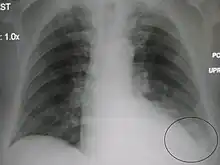

- Normal AP CXR

Normal lateral CXR

AP CXR showing left lower lobe pneumonia associated with a small left sided pleural effusion

AP CXR showing right lower lobe pneumonia

AP CXR showing pneumonia of the lingula of the left lung

Right upper lobe pneumonia as marked by the circle.- Left upper lobe pneumonia with a small pleural effusion.

- Right lower lobe pneumonia as seen on a lateral CXR